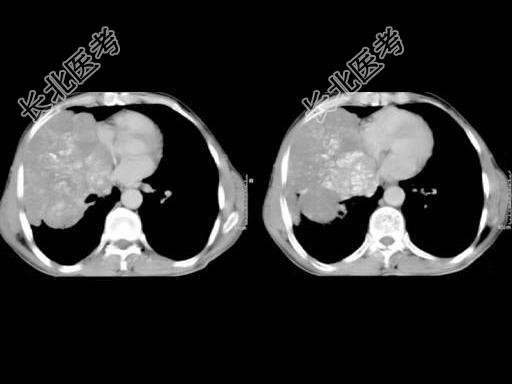

- 单项选择题50岁,男, 右侧胸痛、咳嗽、咯血3月,结合图像, 最可能的诊断是 ( )